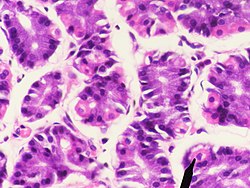

Das Epithel der Magenschleimhaut besteht nur aus einer Zellschicht aus hochprismatischen (höher als breit) Zellen (einschichtiges hochprismatisches Epithel). Die Zellen (Epitheliocyti superficiales gastris) sind durch sogenannte Tight Junctions fest untereinander verbunden. Im Epithel sind zahlreiche schleimproduzierende Nebenzellen eingestreut. Der Schleim dieser Zellen und der der Magendrüsen (s. u.) schützt das Epithel vor der im Magen produzierten Salzsäure.

Die Eigenschicht besteht aus Bindegewebe, Blutgefäßen, Lymphgefäßen, Zellen des Immunsystems (teilweise als Lymphfollikel) und Drüsen. Die Magendrüsen (Glandulae gastricae) münden in die Magengrübchen. Es handelt sich um schlauchförmige (tubuläre) Drüsen. Je nach Magenregion sind diese unterschiedlich ausgebildet und erfüllen auch unterschiedliche Funktionen. Man unterscheidet Kardia-, Fundus- und Pylorusdrüsen. Im Epithel der Magendrüsen sind neben exokrinen Zellen auch endokrin tätige Zellen integriert, die zum diffusen neuroendokrinen System (DNES) gehören.

Fundusdrüsen

Die Fundus- oder auch Eigendrüsen (Glandulae gastricae propriae) bilden den eigentlichen Magensaft. Sie erstrecken sich auf den Magenboden (Fundus) und -körper (Corpus ventriculi). Es sind gestreckte Schlauchdrüsen mit verschiedenen Zelltypen. Diese Schläuche werden in drei Abschnitte unterteilt:

- Isthmus: die Engstelle am Übergang vom Magengrübchen (Foveola gastrica) zum Drüsenschlauch

- Hals (Cervix) des Drüsenschlauches

- Hauptteil (Pars principalis): unterer Abschnitt und Drüsengrund

Die Zellen des Isthmus bestehen zum Teil aus Epithelzellen. Sie bilden, wie das übrige Epithel, Schleim (Mucus) und Bicarbonat-Ionen, die als Basen eine Pufferwirkung gegenüber den freien Protonen haben. Dieser alkalische Schleim schützt das Epithel vor dem sauren Milieu des Magens. Weiter in der Tiefe befinden sich Stammzellen, die sich kontinuierlich teilen und die absterbenden Epithelzellen ersetzen.[1]

Im Drüsenhals kommen vor allem Neben- und Belegzellen vor. Im Hauptteil liegen die Hauptzellen und auch einige Belegzellen.

Die Nebenzellen (Mucocyti cervicales) sind iso- bis hochprismatisch und besitzen einen basalen Zellkern. Sie sezernieren ebenfalls alkalischen Schleim zum Schutz des Epithels.

Die Belegzellen (Exocrinocyti parietales, auch Parietalzellen) liegen zwischen den übrigen Zellen oder ihnen außen an. Sie sezernieren Protonen, die sich extrazellulär mit Chloridionen zu Salzsäure zusammenlagern, und den für die Cobalamin-Resorption (Vitamin B12) notwendigen intrinsischen Faktor. Die Zellen bilden intrazelluläre Sekretkanäle mit Mikrovilli. Diese Kanäle werden im aktiven Zustand der Zellen in die luminale (zum Magenraum gerichtete) Plasmamembran eingebaut und vergrößern so die Kontakt- und Abgabefläche. Hier befinden sich Protonen-Kalium-Pumpen, die Protonen im Austausch gegen Kaliumionen aus der Zelle transportieren. Belegzellen sind relativ groß und eosinophil (mit Eosin anfärbbar und daher rötlich).[1]

Die Hauptzellen (Exocrinocyti principales) im Hauptteil der Magendrüsen sind hochprismatisch mit einem basal liegenden Zellkern. Sie bilden Pepsinogene, die Vorstufen verschiedener Enzyme, die zusammengefasst als Pepsine bezeichnet werden (bei Wiederkäuern das Lab). Sie werden in sogenannten Zymogengranula in den Zellen zwischengespeichert. Hauptzellen sind durch den großen Anteil an rauem Endoplasmatischem Retikulum (rER) basophil (mit basophilen Farbstoffen anfärbbar, daher bläulich).[1]